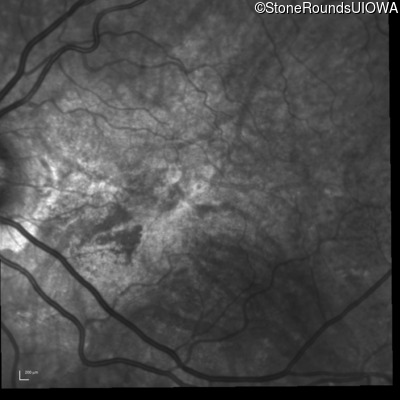

Infrared Fundus Photograph - Right - 20/20 -3 sc

Exemplar